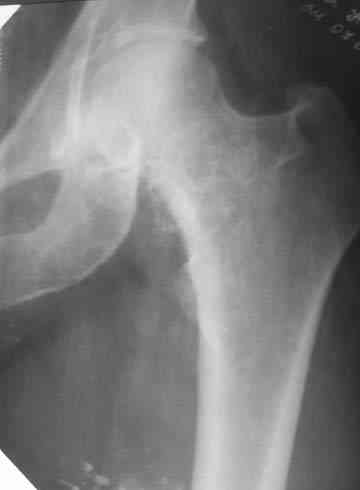

Пациентка И., 1952 года рождения. При первом поступлении пациентка предъявляла жалобы на резкую боль в левом тазобедренном суставе, возникающую при движении.

Боль постепенно усиливалась в течении последних 2 лет. Лечилась амбулаторно у невролога по месту жительства с диагнозом остеохондроз поясничного отдела позвоночника, корешковый синдром. В общих и биохимических анализах крови изменений не отмечалось, ревматоидный фактор (РФ), С-реактивный белок – в пределах нормы. Рентгенологическое исследование. В прямой и боковой проекции левого тазjбедренного сустава отмечается уплотнение крыши вертлужной впадины. В мягких тканях определяются округлой формы участки неравномерного обызвествления.Заключение. ДОА тазобедренного сустава. Хондроматоз слева в мягких тканях.Клиника. Видимых деформаций в области тазобедренного сустава нет. Ограничено отведение в левом тазобедренном суставе из-за болей до 20º. На основании клинических и лабораторных показателей был поставлен диагноз "Хондроматоз левого тазобедренного сустава". После стандартного предоперационного обследования выполнена диагностическая артроскопия тазобедренного сустава – обнаружены свободно лежащие внутрисуставные хондральные тела > 2 см в диаметре, хондромаляция хряща головки бедренной кости II степени. Выполнена боковая артротомия, внутрисуставные тела удалены, синовиальная оболочка частично резецирована. Послеоперационное течение – без осложнений. Швы сняты в срок, заживление первичным натяжением. Назначен курс лечебной физкультуры. Учитывая наличие рентгенологических признаков коксартроза, проведен курс внутрисуставной вискосуплиментарной терапии препаратами 1% гиалуроновой кислоты № 2.Осмотр через 1 месяц после оперативного лечения. Жалоб на боль при ходьбе нет, движения в полном объеме. Рекомендовано динамическое наблюдение раз в полгода и контрольная рентгенография через год